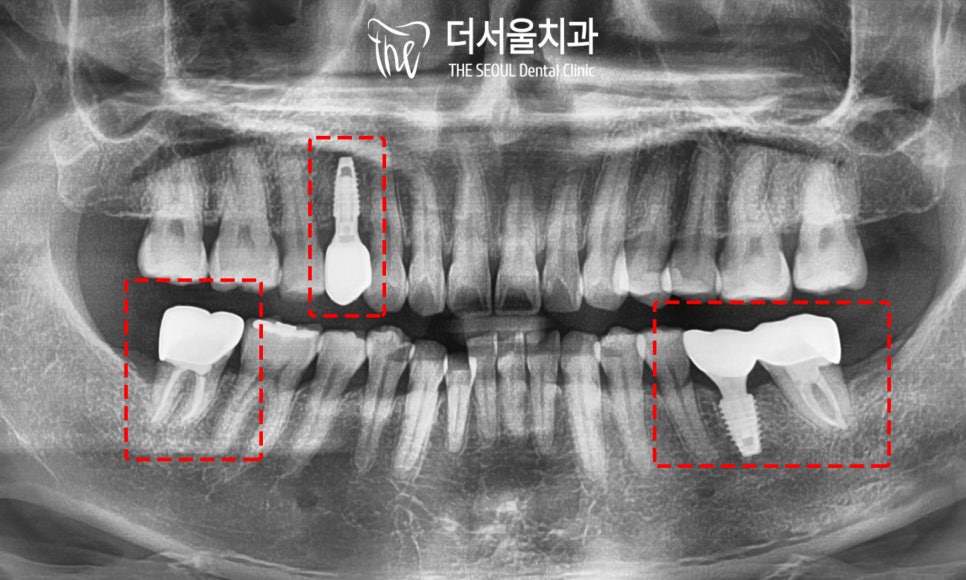

『진단 및 계획』

음 그런데 문제는 하나가 아니네요.

이미 빠져있는 치아도 존재했으며

심하게 썩은 곳도 볼 수 있었습니다.

상악에서는 검게 남아있는 잔존 치근과

군데군데 썩은 곳들이 눈에 띄는데요.

하악도 마찬가지였습니다.

이미 상실되어 빈자리로 남아있는 어금니와

심하게 썩어있는 사랑니,

이외에도 크고 작은 우식을 발견할 수 있었죠.

전체적으로 상황이 좋은 편은 아니었습니다.

『* 전체적인 충치치료

① 사랑니 발치

② 잔존치근 및 치아 상실 부위 임플란트

③ 레진, 인레이, 근관치료를 사용한 우식 제거

<더서울의 계획>』

30대 임플란트 의 마지막 과정입니다.

전과는 달리 검게 썩어 있던 곳들이

모두 개선되어 있는 것을 확인할 수 있습니다.

다행히 골융합은 물론이며

크라운의 형태 또한

주변 인접치들과 잘 어울리는 모습으로

알맞게 제작된 것이 관찰되네요.

크고 작은 충치들도

근관치료, 인레이, 레진을 사용하여

개선해드렷습니다.

30대 임플란트 의 모든 과정이 끝났습니다.